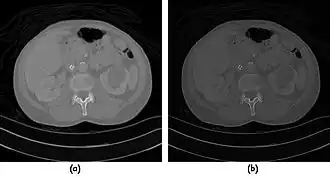

![]() |

- Examples of image display manipulation are shown in the two figures above. In Figure 7.15.2, the same image of a slice through a patient's liver is displayed using a relatively narrow window (high contrast) and also with a wide window. The image with the narrower window appears noisier, but this is merely a reflection of the fact that the gray scale is spread over a narrow range of CT-numbers.

- Figure 7.15.3 illustrates the use of a relatively narrow window to highlight pathology in the lungs.